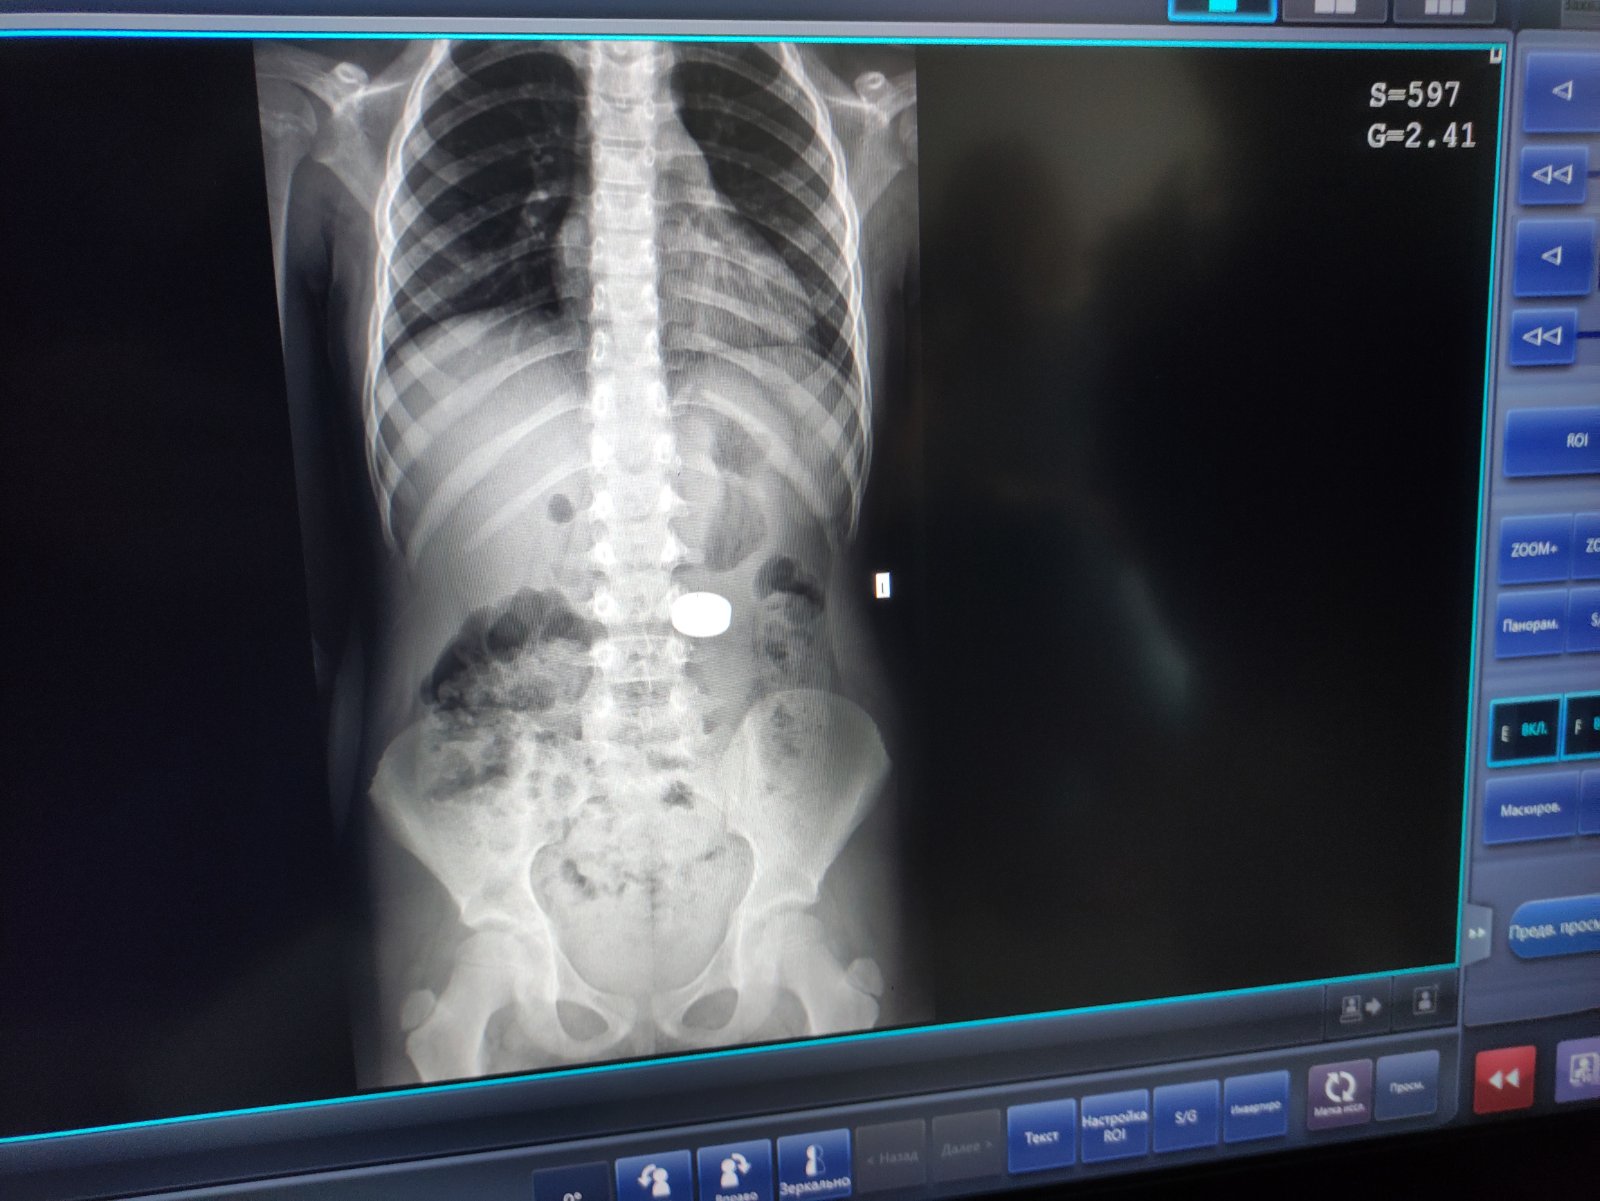

«Дівчинка сама розповіла мамі, що проковтнула магніти. Батьки звернулись у районну лікарню Миколаєва (Львівської обл). Там дитині зробили рентгенографію, і скерували у наш Центр. Ми провели додаткові обстеження, щоб визначити точне розташування стороннього тіла, та дізнатись, чи не виникли ускладнення», – розповіла гастроентерологиня Віта Волощук.

«Магніти були великого діаметру. Під їхньою вагою шлунок опустився до рівня тазових кісток. Тому спочатку візуально вони локалізувались у кишківнику. Проте ми провели пацієнтці додаткове рентгендослідження у лежачому положенні, і зрозуміли, що сторонні тіла ще у шлунку, тож можна видалити їх ендоскопічно», – додав фахівець.